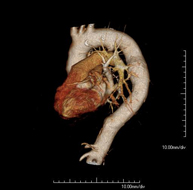

- Abdominal aorta CT angiography

A non-invasive diagnostic test that involves studying the abdominal aorta by obtaining high-definition anatomical images using CT (computed tomography) equipment and iodinated contrast. With the aid of workstations specialised for arterial studies, the image quality supports 2D and 3D reconstructions. It is indicated in patients with vascular disease (atherosclerosis), aortic aneurysms, abdominal pain of possible vascular origin, pre-surgical studies of lesions adjacent to the abdominal aorta as a vascular ‘map’, etc. Information obtained non-invasively is indispensable for patients requiring percutaneous or surgical processing. In patients who only require tracking of vascular lesions, this technique is the non-invasive technique of choice, together with MRI angiography.